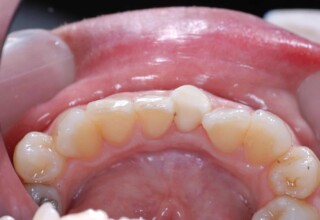

Composite Resin Veneers

Resin veneers are an inexpensive mode of esthetic improvement of anterior teeth, premolars also. Their potential is admirable and their limit is the operator’s clinical dexterity and imagination. In this case there were multiple problems with the upper four incisors: staining, poor inclinations, diastemas, multishading, poor interrelationship and poor tooth-gingiva ratios. They were restored with four direct composite resin veneers (one on a porcelain implant crown!) which were manufactured intraorally!!!